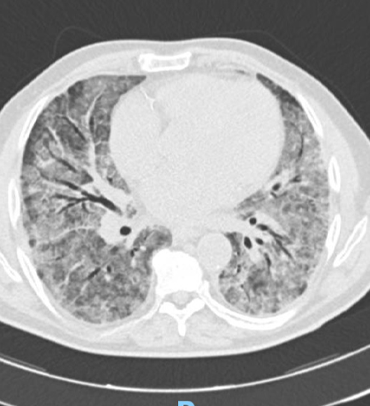

L’evoluzione più grave si ha nei casi in cui si sviluppa la polmonite interstiziale con:

riduzione degli scambi gassosi, ipossia e desaturazione d’ossigeno, espressione d’insufficienza respiratoria che può compromettere l’apparato cardiocircolatorio fino al quadro dell’insufficienza, dello shock e della morte.

IMMAGINI RADIODIAGNOSTICHE